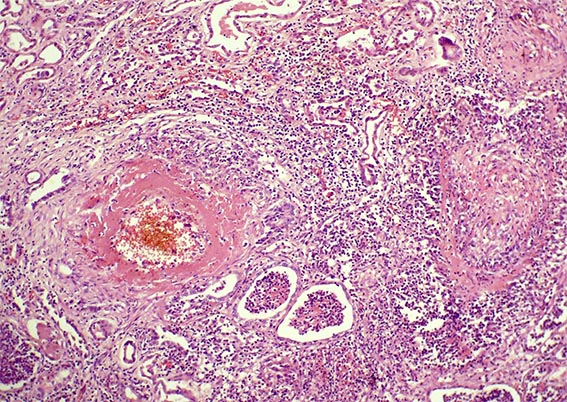

Figura 4. H&E, X100.